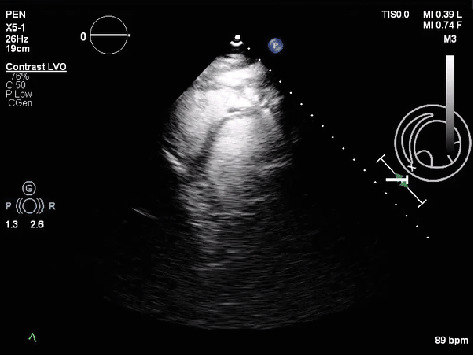

Despite advances in imaging and diagnostics, calcific constrictive pericarditis (CCP) remains a rare and challenging entity, often masquerading as other cardiopulmonary conditions, leading to delayed diagnosis. We present a 70-year-old male with a history of heart failure, atrial fibrillation (AF), cirrhosis, chronic obstructive pulmonary disease (COPD), and prior pleural effusion, who was admitted with acute hypoxic respiratory failure and AF with rapid ventricular response (RVR). Imaging revealed extensive pericardial calcifications, leading to a diagnosis of CCP. The patient's clinical course was marked by refractory hypotension, altered mental status, and progressive cardiohepatic syndrome. Given his high surgical risk, he was managed conservatively and transitioned to palliative care. This case underscores the diagnostic and therapeutic challenges of CCP, particularly in patients with complex comorbidities where surgical intervention is not feasible. It highlights the need for early recognition and individualized management strategies to optimize outcomes in this challenging subset of patients.

Abstract Image